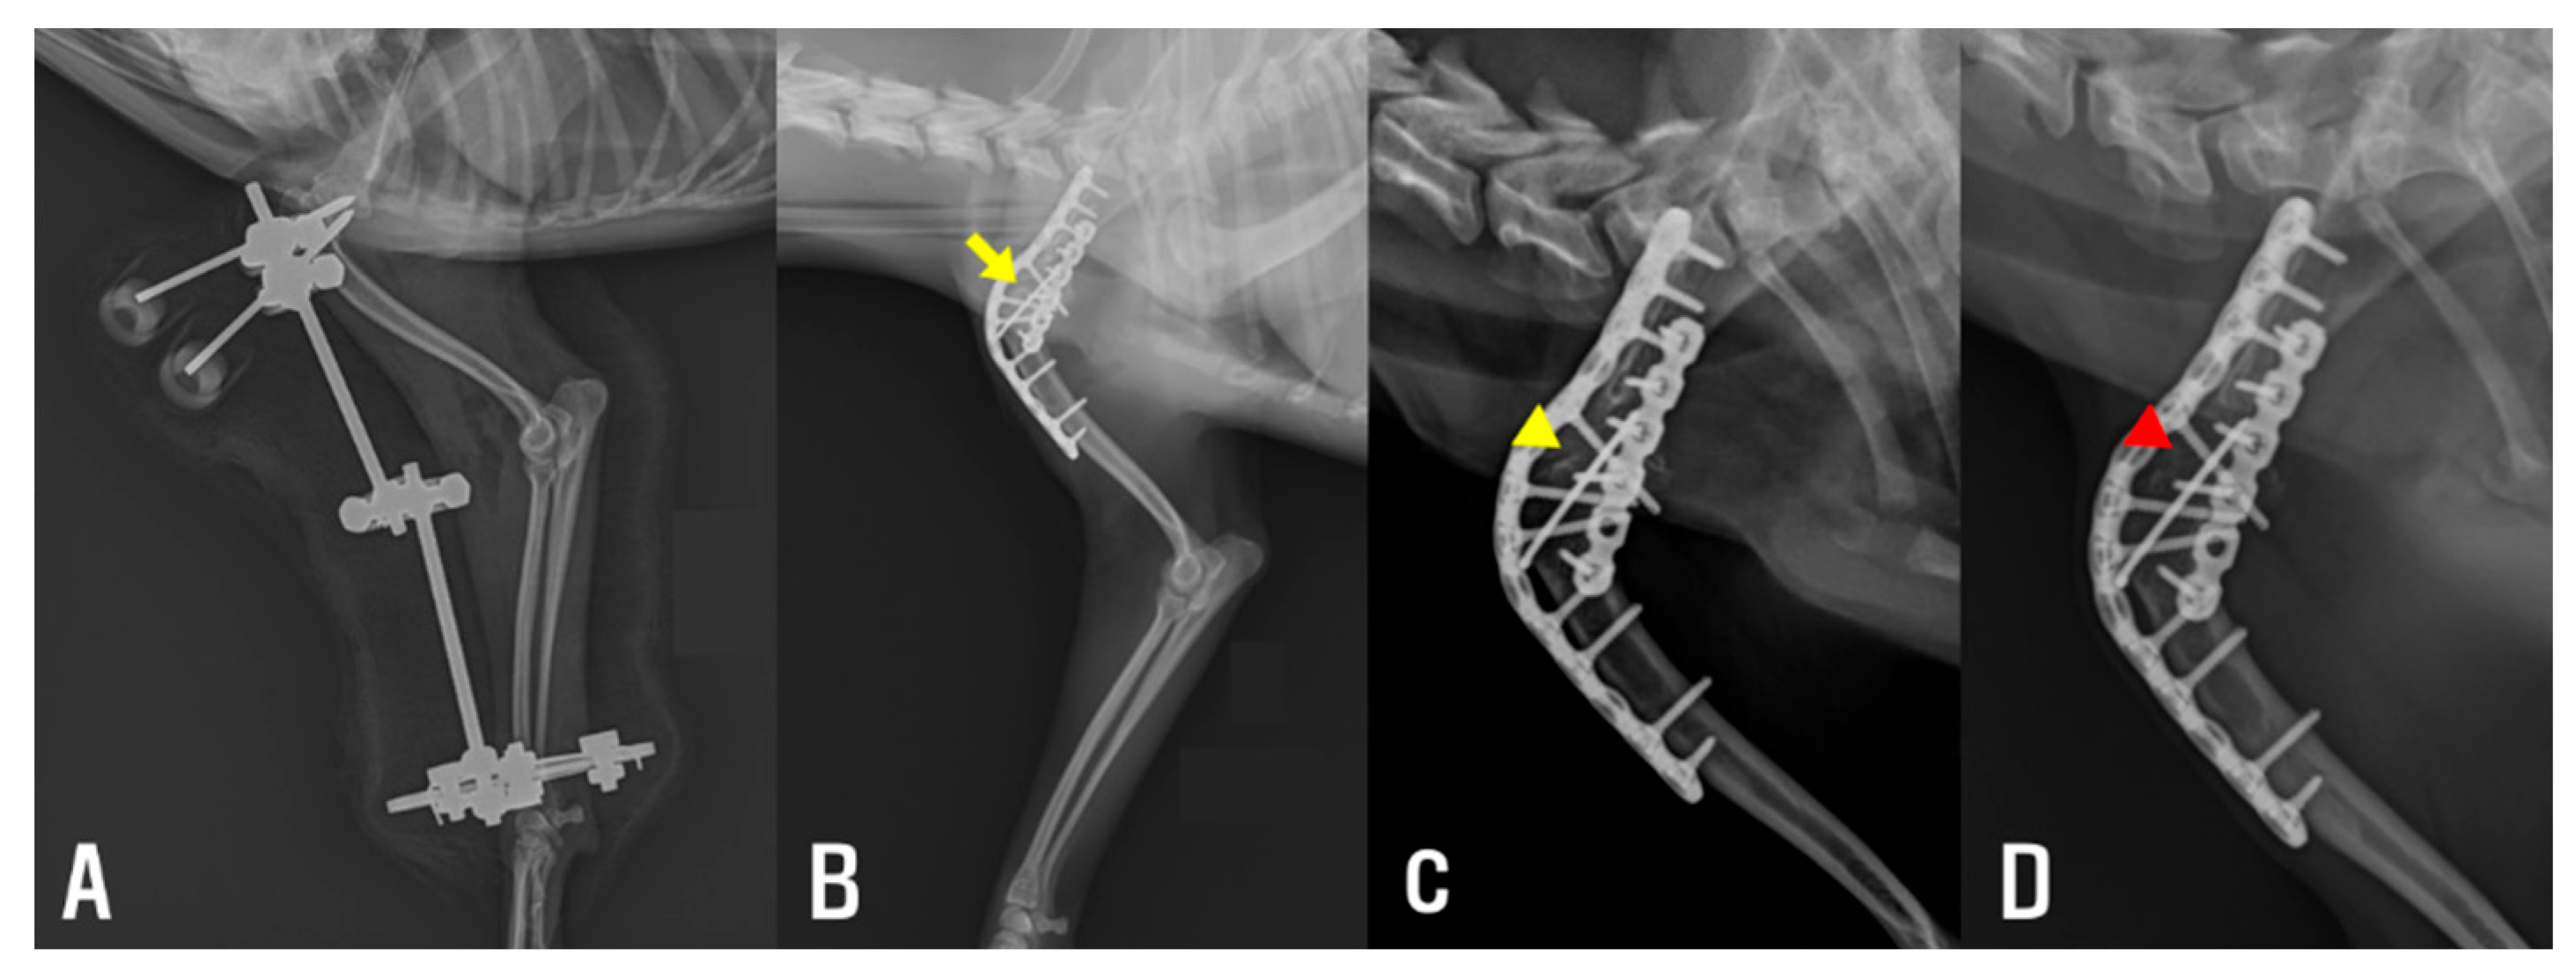

To guide the osteotomy planes and ensure accurate alignment, a 1.6 mm K-wire was inserted perpendicular to the anatomical axis of the scapula, and a second K-wire was inserted perpendicular to the axis of the humerus (Figure 4A). These pins served as independent visual references to maintain proper orientation during circular osteotomy and minimize the risk of angular deformity.

A circular osteotomy was performed at the scapular glenoid cavity and the humeral head, including the greater tubercle using a 12 mm radial saw (Synthes, Oberdorf, Switzerland; Figure 4B,C), to allow controlled adjustment of the limb alignment angle. The joint was then stabilized at an angle of approximately 120°, a position considered appropriate for maintaining functional limb posture during ambulation. Internal fixation was achieved using a combination of a K-wire and two contoured reconstruction locking plates. A single 1.6 mm K-wire was inserted from the greater tubercle of the humerus into the scapular body to maintain the reduction of the osteotomy surfaces and augment stabilization of the bones across the fusion site. Subsequently, internal fixation was completed with anatomically contoured locking plates. A 1.5 mm/2.0 mm poly-axial locking plate (Arix Vet, Jeil Medical Corp., Seoul, Republic of Korea) was contoured and applied to the craniolateral aspect of the scapula and proximal humerus, with screws directed to engage both the scapular spine and body. An additional 1.2 mm locking plate (Arix 1.2; Arix vet, Jeil Medical Corp.) was contoured and applied to the caudolateral aspect of the humerus to augment construct rigidity (Figure 4D).

Figure 4. (A) Left shoulder joint exposed via a craniolateral approach. A 1.6 mm K-wire was inserted into the humerus perpendicular to its anatomical axis (yellow arrowhead), and a second K-wire was placed in the scapula (yellow arrow) in the same manner. These pins served as visual guides to assist in maintaining proper alignment during the osteotomy. The glenoid cavity of the scapula is indicated by the yellow arrow, and the humeral head is indicated by the yellow arrowhead. (B) Circular osteotomy of the articular surfaces performed using a radial saw. (C) Articular surfaces removed, and concave–convex interface prepared for fusion. (D) Shoulder joint stabilized with a bone plate following alignment and compression of the osteotomized surfaces. Cr, cranial; Cd, cauda; Pr, proximal; Di, distal.